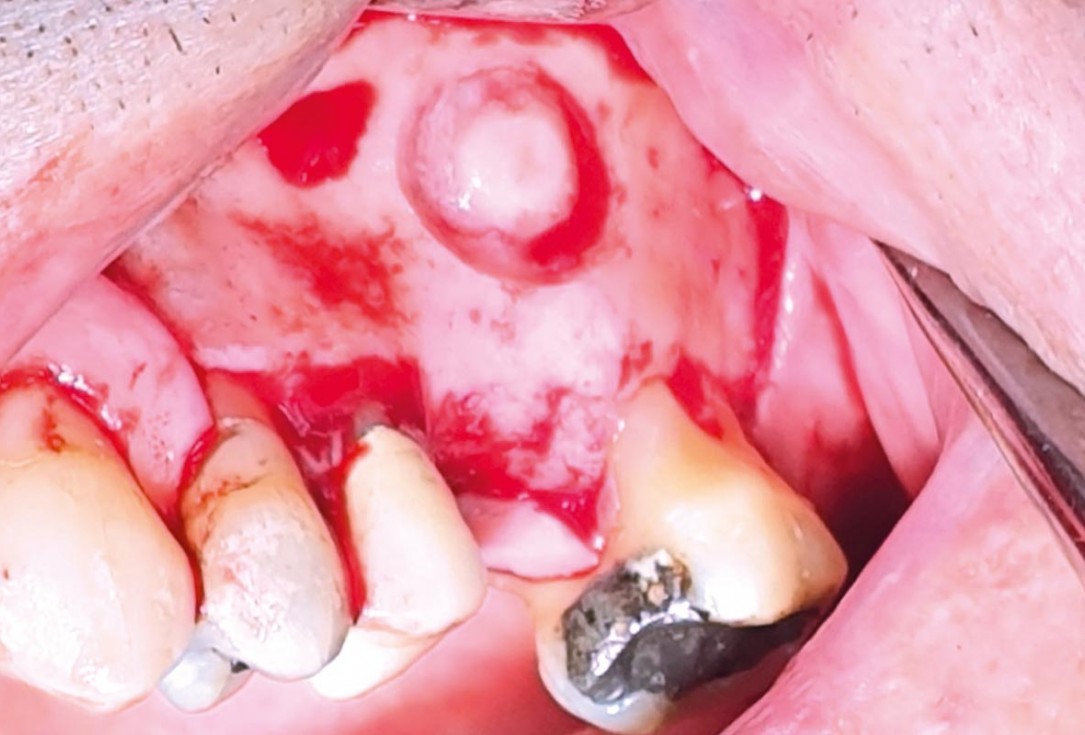

04/35 - Preparation of the lateral sinus window using piezosurgeryMaxillary sinus cyst removal using the Crocodile Technique and subsequent lateral sinus lift - Dres. C. Scognamiglio and A. Perucchi